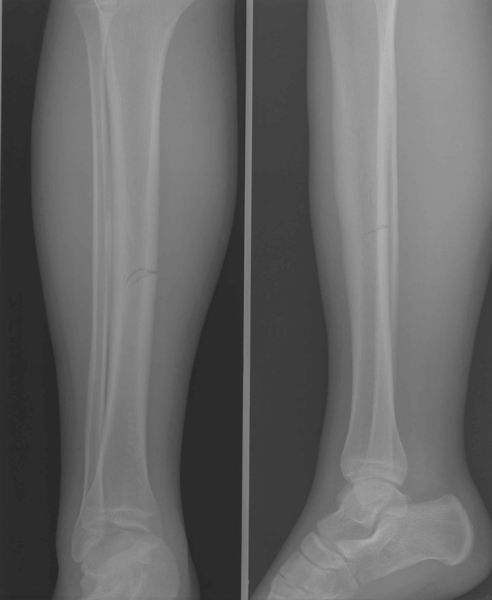

Thorax – Abdomen – Schedel – CWZ – DWZ – LWZ – Bekken – Full Spine – Schouder – Bovenarm – Elleboog – Onderarm – Pols – Hand – Heup – Bovenbeen – Knie – Onderbeen – Enkel – Voet – Full Leg – Transit – Colonografie – E.R.C.P. – I.V.P. – Cystografie – Hysterografie

Enkel